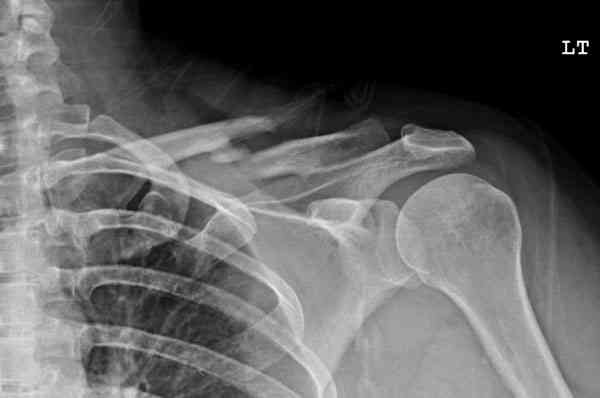

Недавно разбирали случай ложного сустава.

45 летная женщина после автоаварии, алкоголь 163 и 20 летним стажем курения.

Консервативное лечение, через 8 мес. операция Rockwood pin с костной пластикой в нашем городе другим врачом. После 8 недели падение, гвоздь удален оперирующим хирургом, больная направлена к нам. Фиксация реконструктивной пластиной с трикортикальным графтом, добавлен BMP-2. Для стабилизации фиксацию провели через акромион.

Вот уже два месяца больная также продолжает жаловаться на боли, буквально на днях удалили акромиальную часть пластины с специальной пилой с алмазным покрытием для медицинского металла. До сих пор судьба ложного сустава неизвестна....